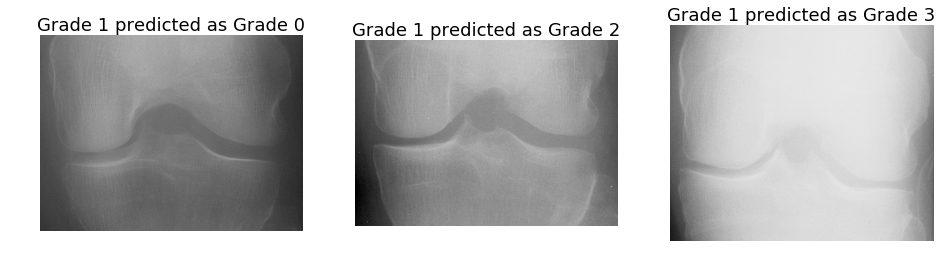

Automatically localising the knee joints in X-ray images is an important and an essential step before quantifying knee OA severity. Previously, template matching was implemented as a baseline method to localise the knee joints, proposed by Shamir et al. [1, 3], and it was shown that the detection accuracy is low (30%similar-toabsentpercent30\sim 30\%) in this method for large datasets like OAI. To improve the localisation, a SVM-based method with Sobel horizontal image gradients as features was proposed in this Section. This method showed a large improvement in detection accuracy (82%) but still falls short of perfect localisation. The anomalies in localised knee joints can affect the step involving classification of the localised knee joints to quantify knee OA severity.

Instead of using hand-crafted features, a deep learning-based solution was proposed in this Section to further improve localisation. FCNs were trained to automatically detect and extract the knee joints. All three methods: template matching, SVM-based and FCN-based were evaluated using a common metric: the Jaccard Index. This method achieved almost perfect detection with 100% accuracy for a Jaccard Index 0.5 and an accuracy of 92% for a Jaccard index greater than equal to 0.75. The author believes this performance is sufficient to localise and extract the knee images for classification. As such further improvements are left as future work. The localisation performance may be improved by including additional pre-processing steps to remove the artefacts and noise in the images, and to normalise the local contrast variations in the images. Using additional data for learning and data augmentation may improve the localisation performance.

5 Automatic Assessment of Knee OA Severity